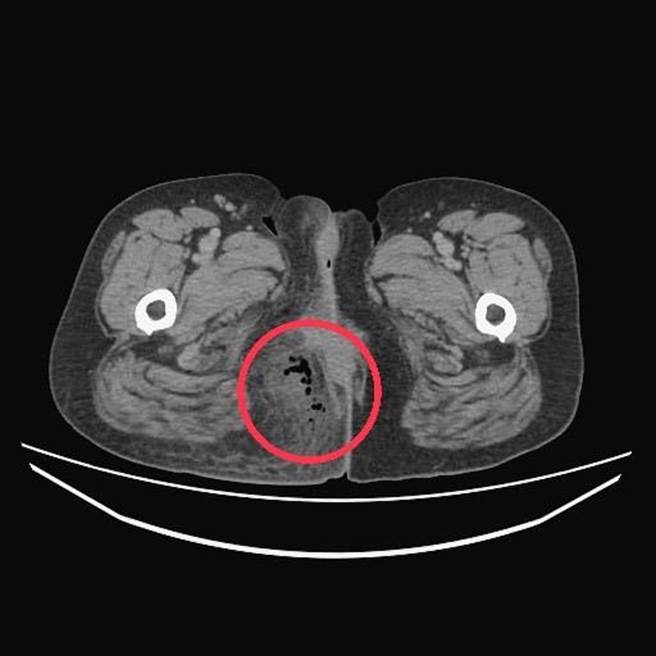

台中55岁阿秀日前因误吞3公分鱼刺,造成鱼刺卡在肛门周边组织,红肿疼痛不止。(台中医院提供/潘虹恩台中传真)

台中医院消化外科、全静脉医学主任医师曾旭弘表示,患者当初并未提到饮食问题,因此未思考异物侵入的可能,直到患者肛门组织发炎严重紧急施作清创手术,切开患部才发现3公分鱼刺刺入患者肛门右侧组织,导致发炎坏死;手术开了约6公分的切口,考虑到伤口照顾不易,决定让患者施打「全静脉营养针」,并辅以「高压氧」缩小手术伤口。